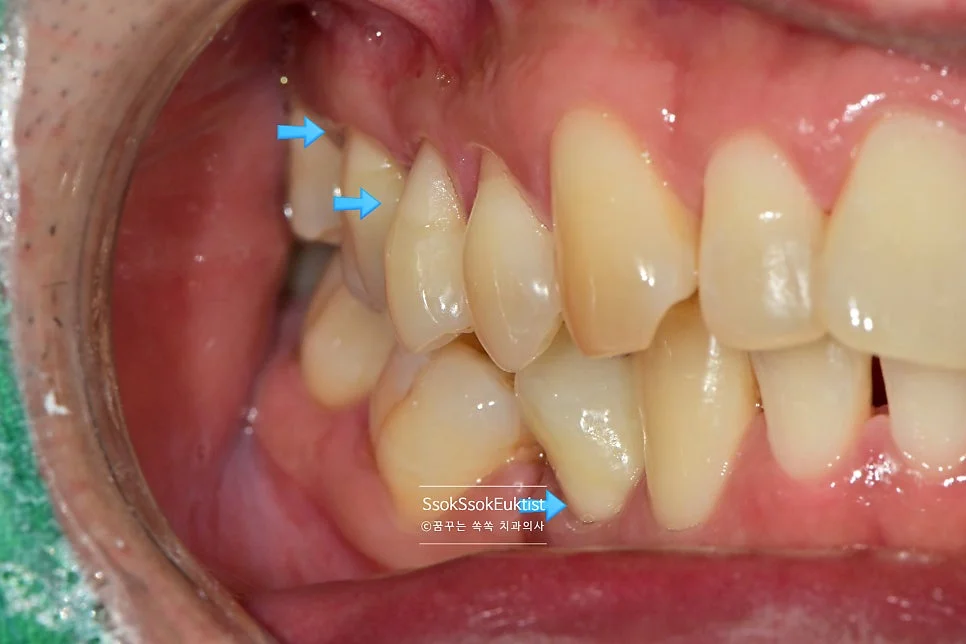

GI 치료 전 — 대부분 V자, 일부 U자 형태

형태를 보면 대부분 V자인데 하나 정도만 U자 형태를 보이고 있습니다. 이런 경우 강한 칫솔질이 치경부 마모증을 악화시켰다고 볼 수 있습니다!

화살표로 표기된 치료 계획 — 앞쪽은 레진, 어금니는 GI

화살표로 표기된 것과 같이 눈에 보이는 앞 쪽 치아는 레진으로, 큰 어금니는 GI로 계획을 세웠는데요.